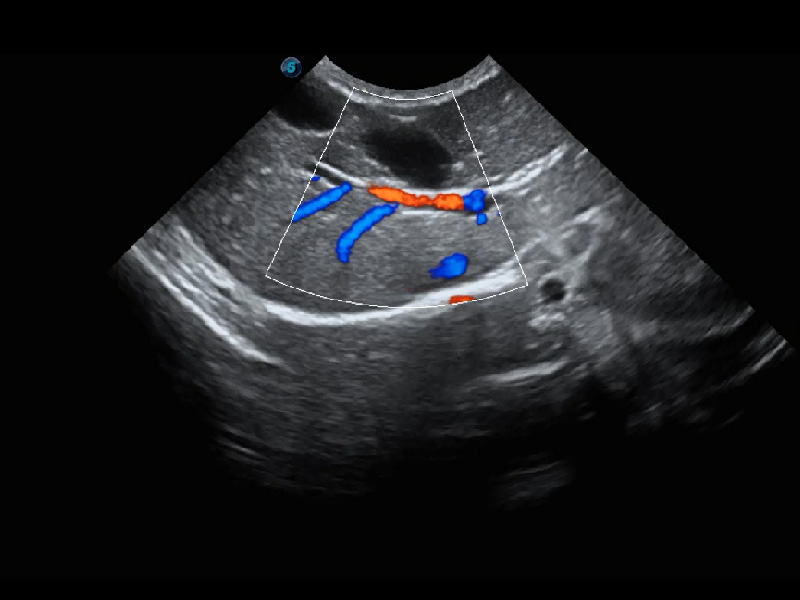

ProPet 60 作为一款高端台式动物超声设备,为动物医生的日常诊断提供了一系列贴合动物临床需求、解决临床实际问题的高级成像功能。凭借全系列高清探头,满足医生对腹部、心脏、生殖、浅表、肌骨等成像的所有需求,切实帮助您提升检查效率,提高诊断信心。

动物是人类最亲密的朋友和最值得信赖的伙伴。16877太阳集团也一直致力于探索动物专用的超声影像解决方案。 全新推出的ProPet系列,是16877太阳集团在动物超声影像智能化、专业化、精准化的一次跨越式革新。动物不能用言语来表述自己的不适,通过超声影像,ProPet系列搭建了动物医生与不同物种沟通的“桥梁”,为动物医生注入了“治愈之力”。